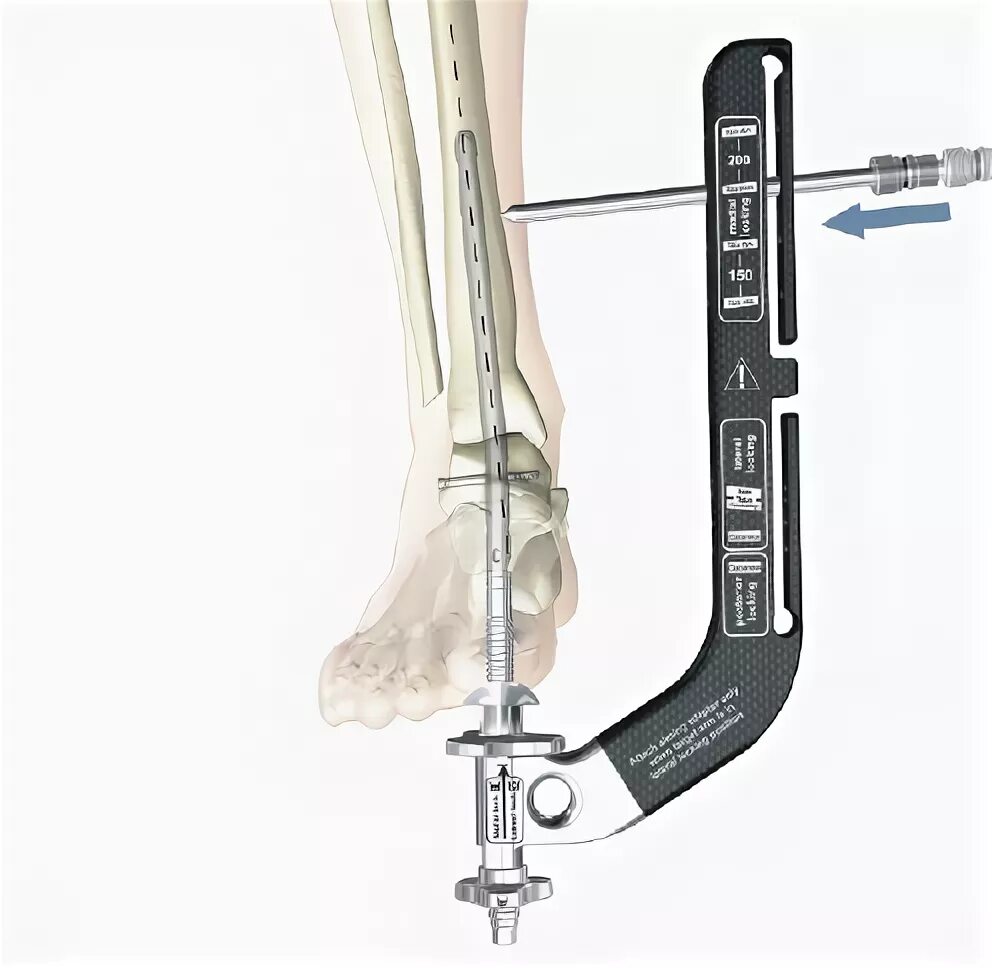

Артродез форум